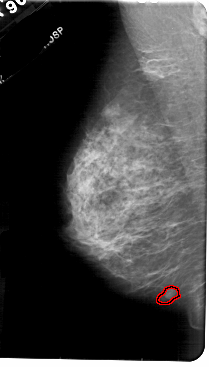

A_1842_1.LEFT_MLO

LEFT_MLO LINES 5491 PIXELS_PER_LINE 3121 BITS_PER_PIXEL 12 RESOLUTION 43.5 OVERLAY

FILE: A_1842_1.LEFT_MLO.OVERLAY

TOTAL_ABNORMALITIES 1

ABNORMALITY 1

LESION_TYPE MASS SHAPE LOBULATED MARGINS CIRCUMSCRIBED

ASSESSMENT 4

SUBTLETY 3

PATHOLOGY BENIGN

TOTAL_OUTLINES 1

BOUNDARY